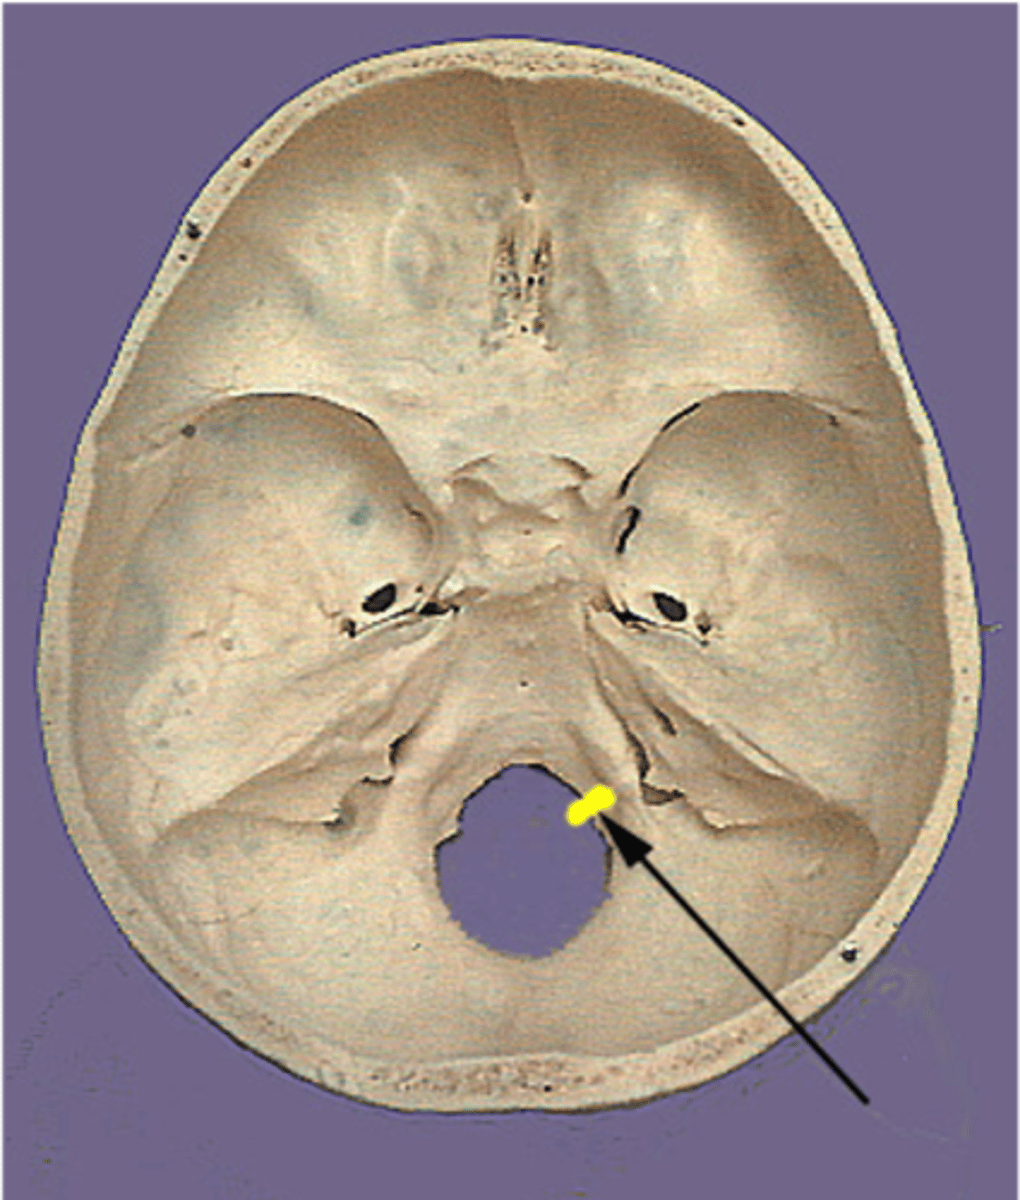

What artery passes through the foramen spinosum?

Middle meningeal artery

The middle meningeal artery passes through what foramen?

Foramen spinosum